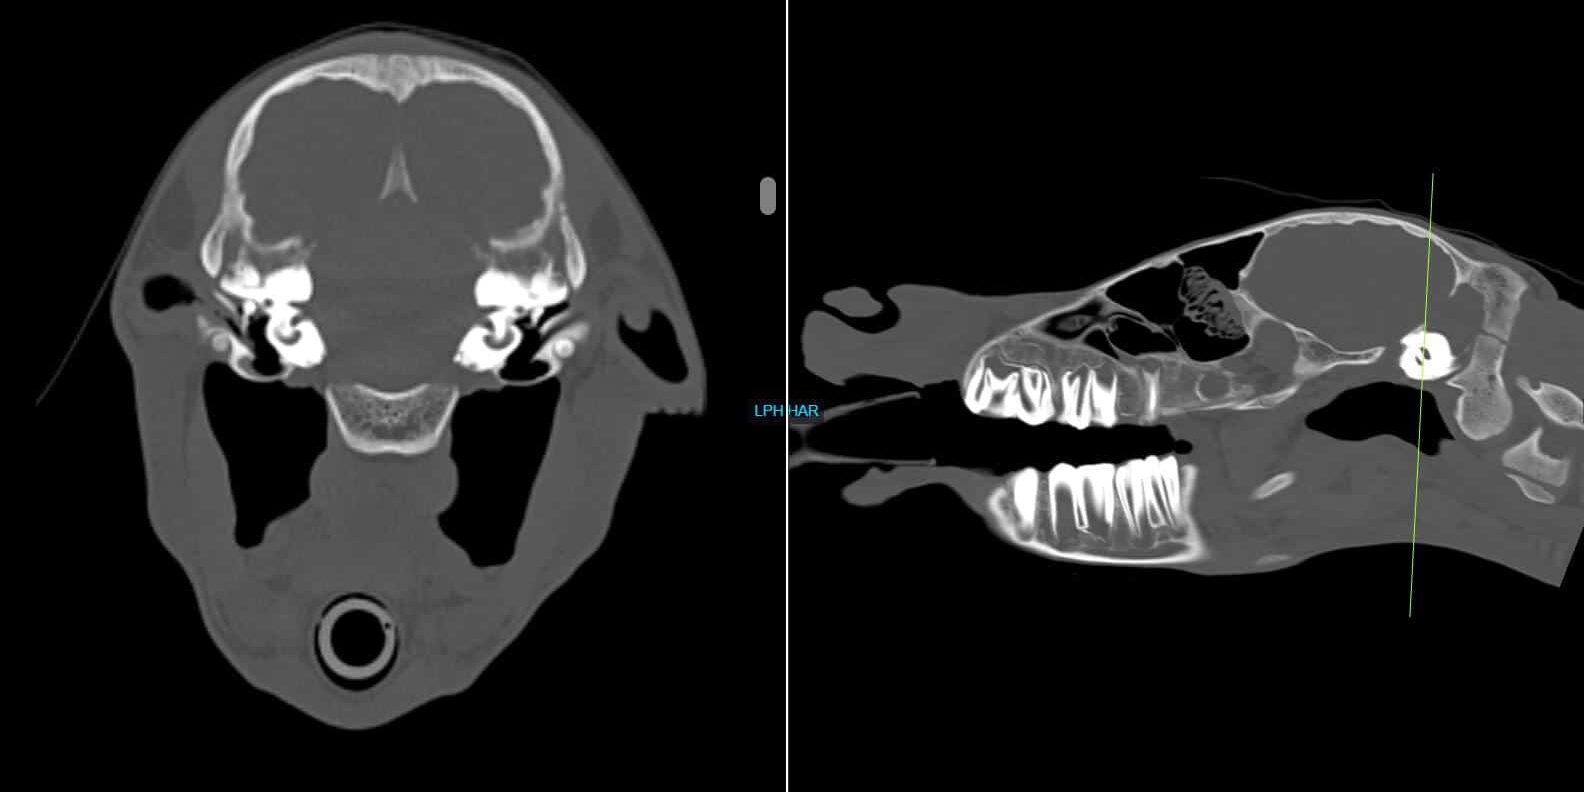

Nova, an 8-day old Quarter Horse filly, presented to Animal Imaging following a 2-day history of right sided head tilt with no known evidence of trauma. She was worked up by a boarded internal medicine specialist who found no significant abnormalities on physical examination, bloodwork, and initial radiographic findings. The filly presented for head and neck computed tomography (CT) to look for a possible cause of the head tilt and initial scan findings were relatively unremarkable aside from the appearance of debris seen within the right middle ear (blue arrow). Due to the lack of significant findings and the owner’s goals of identifying any significant performance limiting abnormalities within the foal, she was then taken to magnetic resonance imaging (MRI) for same day brain imaging. The collected images are shown below:

These images show cross sectional images of the skull of the foal. The image on the left shows a cross section taken from the area of the green line on the right-side image. As you can see with the blue arrow, the area of the right middle ear (right of the horse is on the left of the image) is grayer as compared with the clear area of black within the ear canal on the left of the horse. For this reason, MRI was elected to further evaluate this potential area of concern.